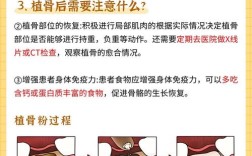

- 骨愈合期: 这是最关键也最需要耐心的时期,通常需要4-9个月不等,具体取决于骨缺损大小、移植材料类型、患者自身条件,期间需定期复查。

- 种植体愈合期(骨结合期): 种植体植入后需要3-6个月的时间与颌骨牢固长在一起(骨结合),期间避免种植体受力。

- 定期复查与维护: 终身维护! 需要严格按照医生要求定期复查(通常每3-6个月一次),进行专业洁牙,并掌握正确的家庭口腔卫生维护方法(刷牙、牙线、冲牙器等),预防种植体周围炎。